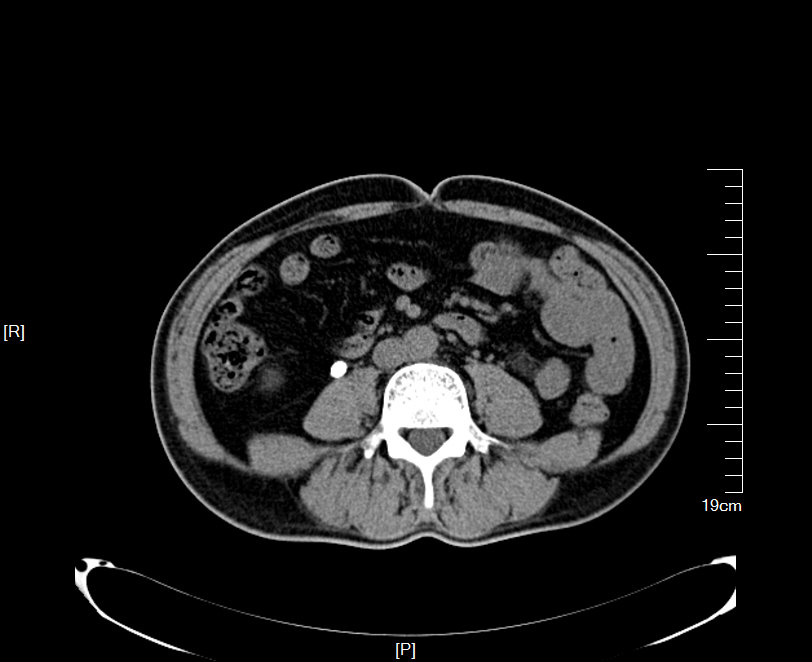

2016年04月手术患者,女性,32岁,昆山人,五年前曾因右输尿管结石引起肾绞痛于当地消炎补液解痉排石处理,疼痛缓解后未于重视,其间从未予复查,2周前出现右腰痛,与当地诊所就诊后予以震波碎石无效,并出现发热,急诊来我院就诊,CT:右肾萎缩,右侧肾脏积水,右侧输尿管多发结石形成石街约4.5*1.5cm,GFR:右侧17.2ml/min,左侧43.2ml/min。因左侧健肾代偿,肾功能正常:Cr 132umol/L;术前诊断:右输尿管下段多发结石 右肾萎缩 肾功能不全,鉴于右输尿管结石梗阻时间太长,肾功能不全,已处于失代偿期,最终也只能行右侧输尿管下段切开取术,解除输尿管下段梗阻,尽可能保护已经萎缩的肾脏,该患者预后不良。

增强CT检查提示:右侧肾脏积水,右肾萎缩,右输尿管下段多发结石

KUB提示右输尿管下段结石呈石街样排列,引起右输尿管完全梗阻,导致右肾萎缩